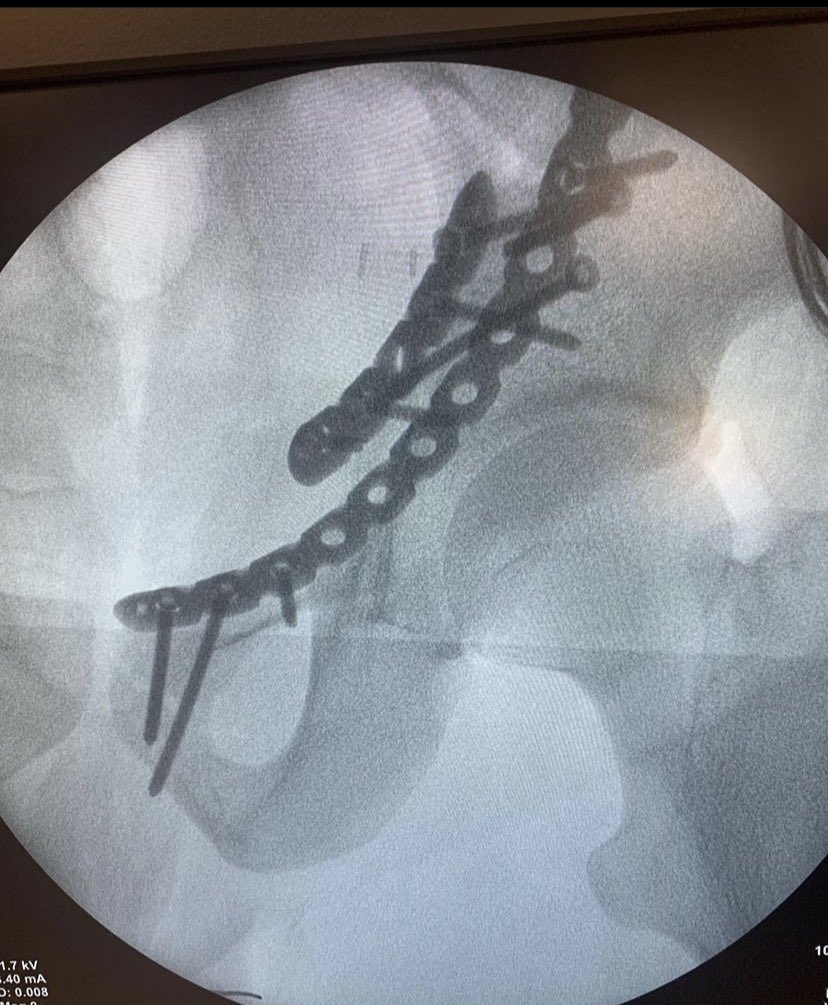

47 years old male patient, neglected (3 mounths) multilevel thoracolumbar junction spine fracture (L1, T12 and endplate of T11). there is monosegmental pure osseous failure of the posterior tension band in T12. this also called "Chance" fractures. #spinesurgery #spine